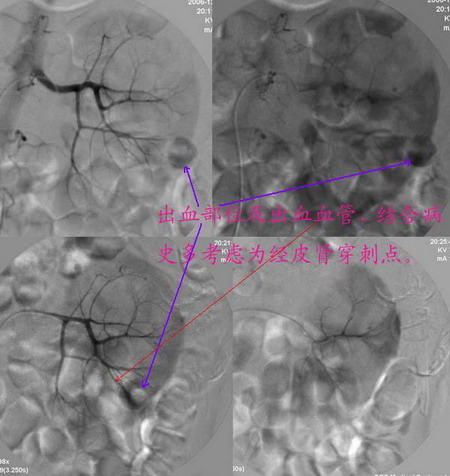

男性,45岁,因左输尿管与肾盂结合部结石住院治疗,经皮肾镜治疗失败后,改做开放手术.手术后3天出现血尿,5天保守治疗仍不能止血,申请肾动脉dsa,见下图片,发帖目的在于请各位分析判断出血部位.

介入治疗过程:

注:图5\6文字标示应为".....再次证实出血部位"

病史已说明肾盂和输尿管交界处结石,穿刺时首先经过包膜--肾实质--肾盂,这样就会有一潜在的通道,包膜下的出血可以延着通道渗入至肾盂、输尿管,所以就有血尿了。